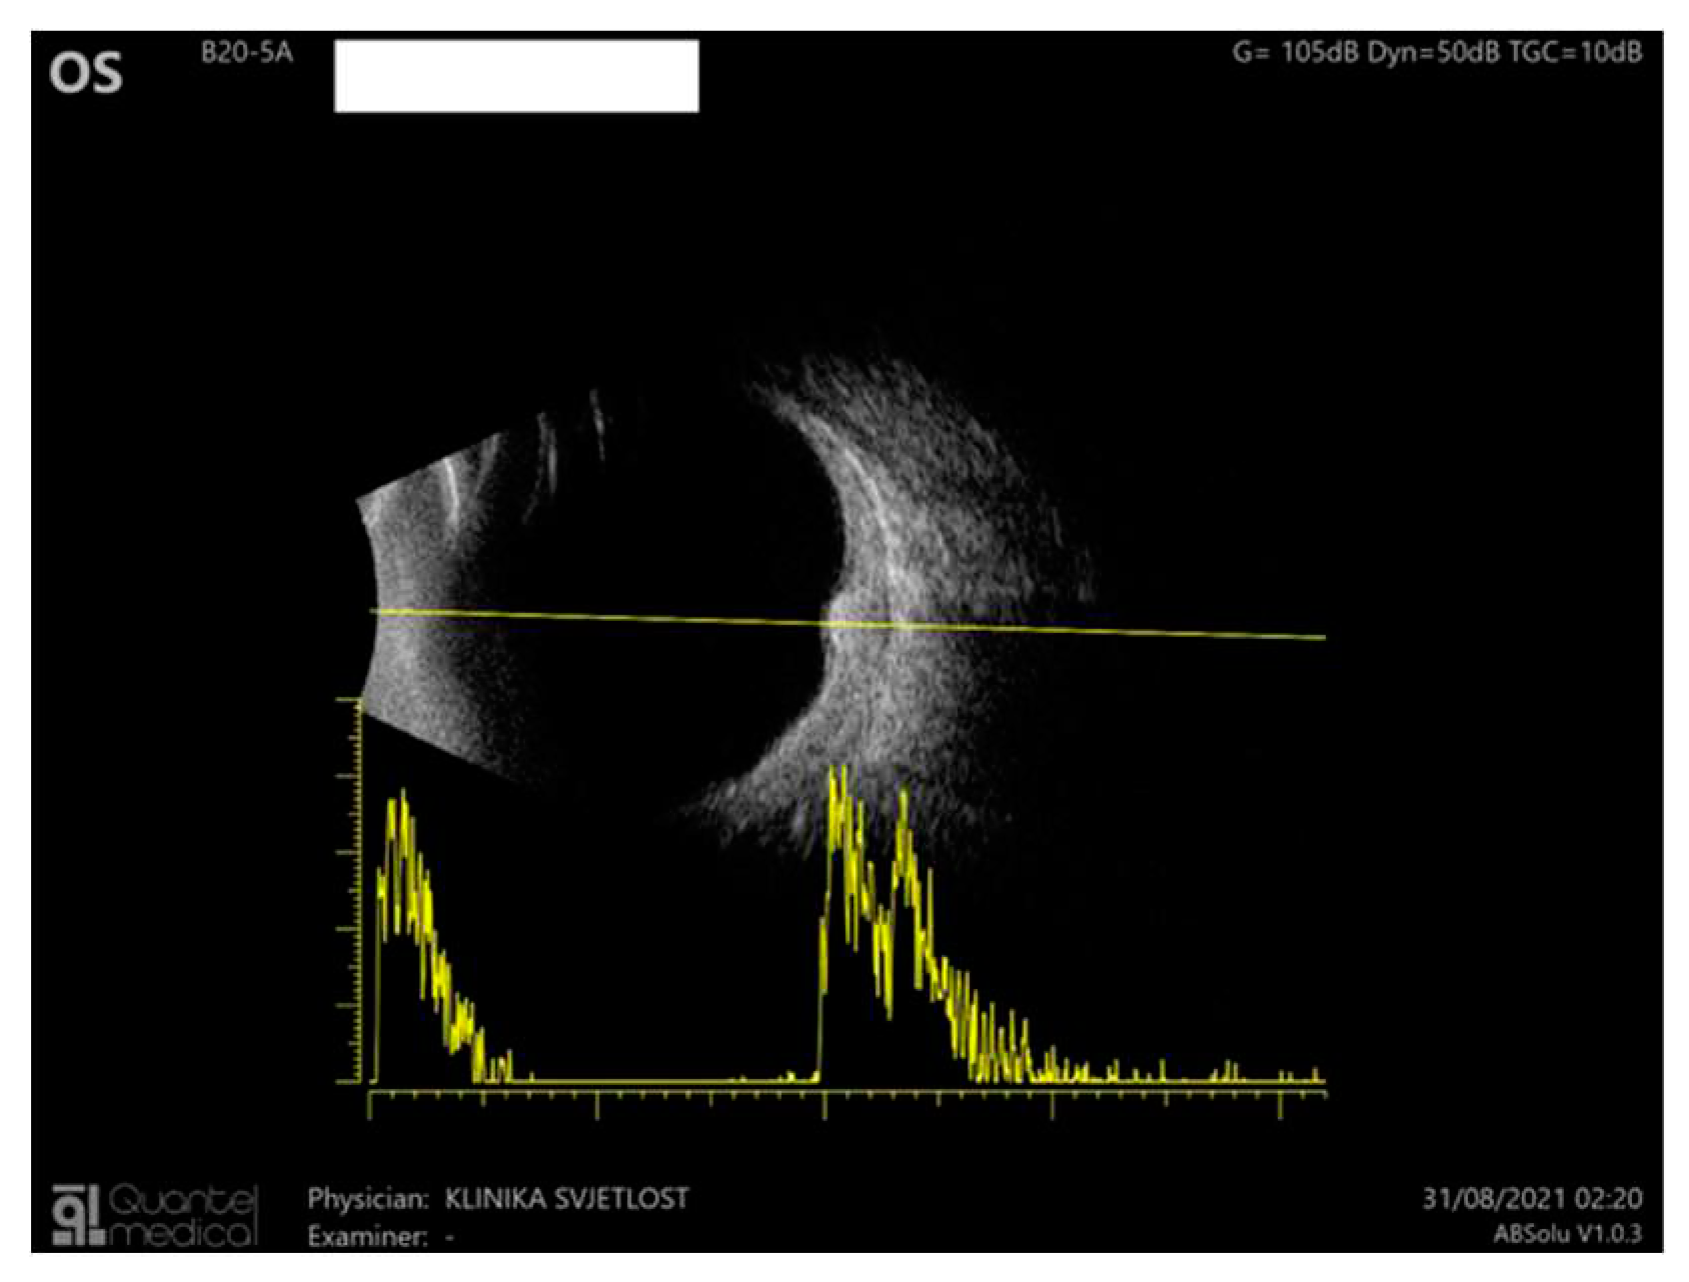

B-scan ultrasound through the choroidal lesions showed moderate homogenous internal reflectivity (Figure 3).

Figure 3. Ultrasound of the LE: B scan demonstrates moderate internal reflectivity through the lesion and diffuse choroidal thickening.